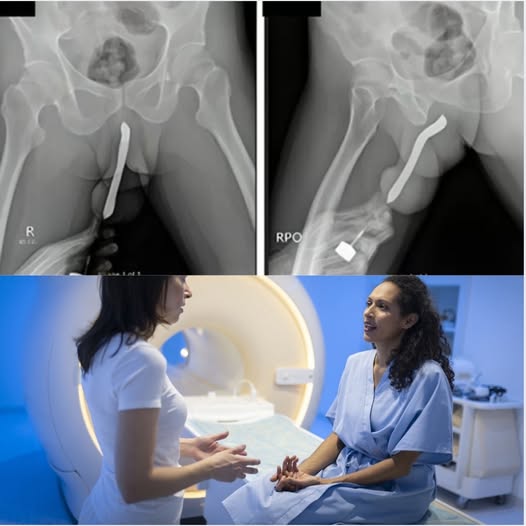

A recent case that gained attention online highlights the importance of teaching young people about safe health practices and body awareness. According to hospital officials, a teenager required urgent medical care after attempting to use an object in an unsafe way, which resulted in serious internal injury.

Doctors at the hospital acted quickly, performing an emergency procedure to remove the object and stabilize the patient’s condition. Thanks to timely intervention, her health has now been secured.

The case serves as an important reminder: never insert or use objects that are not medically designed for the body. Doing so may cause permanent damage, infections, or require surgery.